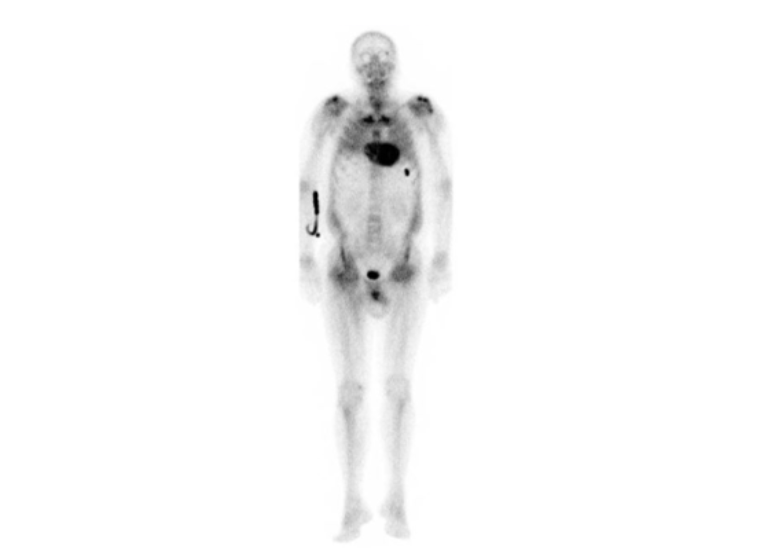

- Whole-body SPECT/CT for bone scintigraphy (99mTc-DPD): intense fixation of the radiopharmaceutical with particular involvement of the septal and lateral regions of the left ventricle associated with fixation in the right ventricle associated with marked global reduction of uptake in the skeletal area (Perugini Score: 3).

Bone scintigraphy showing Perugini score grade 3

Definitive diagnosis requires histological confirmation of the presence of amyloid substance on biopsy specimens obtained from tissues involved in the infiltrative process. In recent times, nuclear imaging has revolutionized the diagnosis of ATTR amyloidosis. Bone-specific radioisotopes used in total body bone scintigraphy bind transthyretin amyloid deposits. The degree of myocardial accumulation is variable and visually determined by the Perugini score (from 0 = no accumulation to 3 = pathological myocardial accumulation, greater than bone accumulation). In patients with score 2-3, in the absence of laboratory signs suggestive of AL amyloidosis, the non-invasive diagnosis of ATTR amyloidosis is possible with specificity and sensitivity greater than 99%. Subsequent genetic analysis will allow the distinction between mutant and wild-type forms.